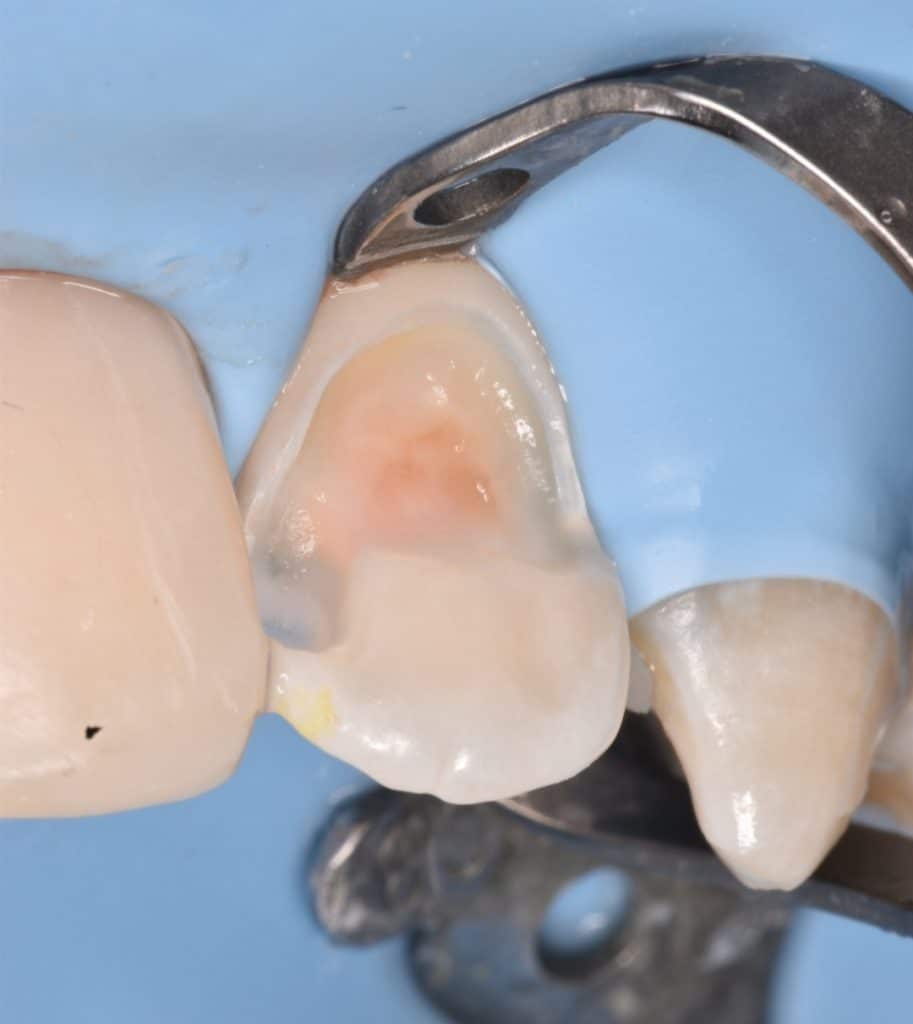

Isolation

Cavity prep.

IDS with gold standard SE bond

RC by flowable composite

DWT

APX composite used for dentin replacement and tokuyama composite for enamel replacement